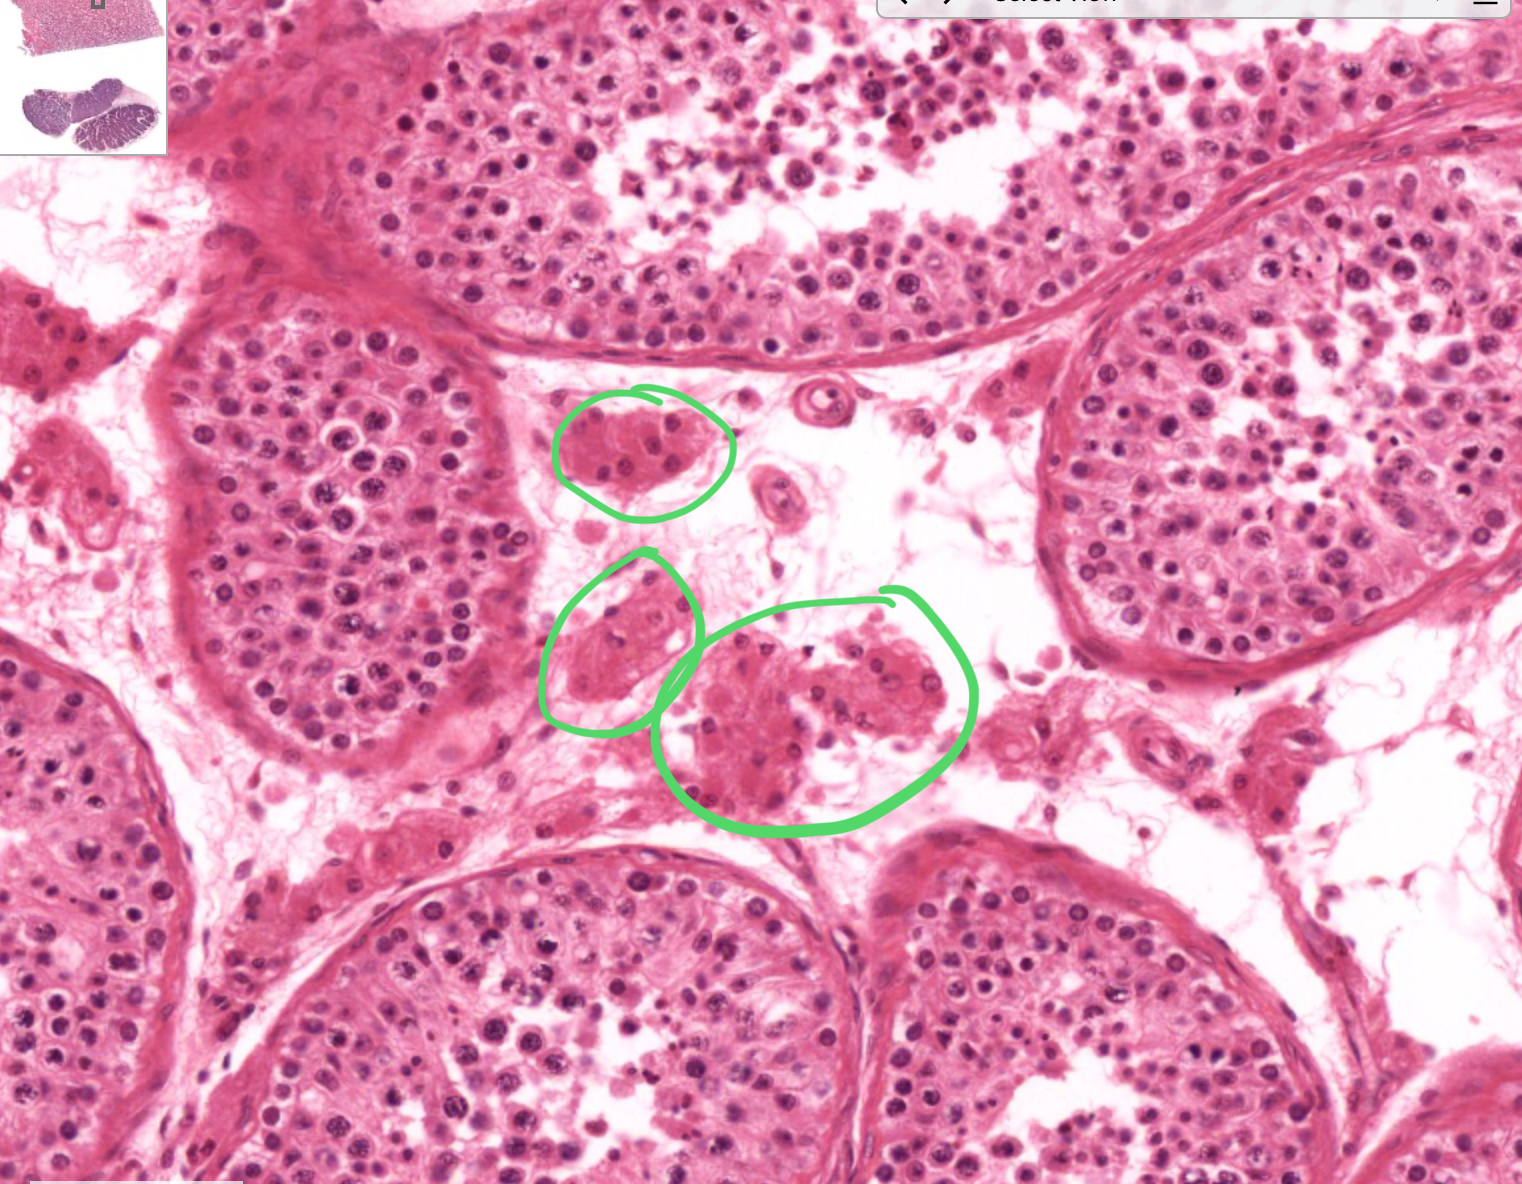

histo; “clumps” between circles

leydig cell

histo; larger nucleus but pretty solidified

spermatogonia

histo; large nucelus, but starting to break apart, can see little dots in the nucleus

primary spermatocyte

histo in general;

spermatid

histo specific; small condensed dark nucleus

spermatid-early

histo specific; flattened long nucleus and cell

spermatid-late

histo; flattened nucelus and cell but within the mess, has tails

spermatozoon